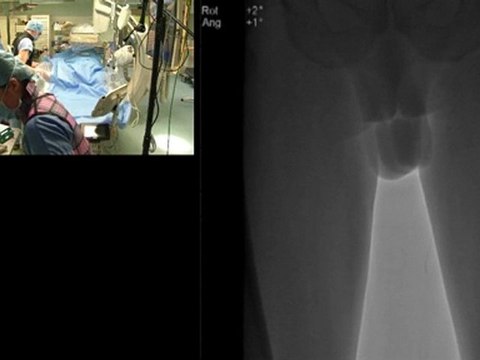

14 right vertebral artery stenting occluded left vertebral artery incathlab.com

right, vertebral, artery, stenting, occluded, left, incathlab